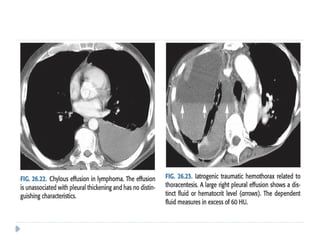

 Chylothorax:

 A chylothorax contains fluid that is largely chyle (lymph of

intestinal origin).

 Because chyle usually contains suspended fat in the form of

chylomicrons, chylothorax fluid may be milky.

 Three main mechanisms account for chyle collections in the

pleural space: (i) leakage from a discrete rupture of the thoracic

duct or a large lymphatic vessel

(ii) a general oozing from pleural lymphatics,

(iii) passage of chylous ascites through the diaphragm

 Approximately 50% of chylothoraces are of neoplastic origin

 25% are traumatic,

 15% are idiopathic

 Lymphomas make up about 75% of the neoplastic lesions , and

chylothorax can be the initial feature of lymphomas

 Hemothorax:

 Bleeding into the pleural space

 may be secondary to trauma, aortic rupture, or pleural malignancy.

 Occasionally, it is seen in thromboembolic disease when

complicated by pulmonary infarction.